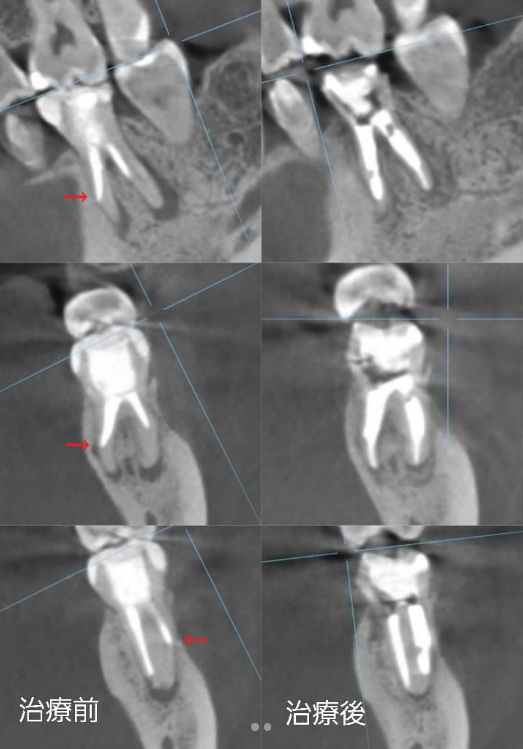

以前治療しました患者さんのCT画像を見てみましょう。

左の治療前の画像で、赤い矢印で示されているのは、本来の根(神経)とは違う方向へ突き抜けてしまっている箇所です。

前医で違う方向へ進められ、パーフォレーションを起こし、その方向へ根管充填されています。

そのために患者さんは歯ぐきの腫れを繰り返していました。

当院で治療をやり直しました。

パーフォレーションリペアといって、穴の開いた箇所には「MTAセメント」という回復させる薬剤を使用して埋めています。そして本来の神経の方向へ修正して根管充填を行っています。

治療前は、歯の周囲に黒く炎症の影が見られますが、治療後の画像では周囲の影は消え、完治しています。